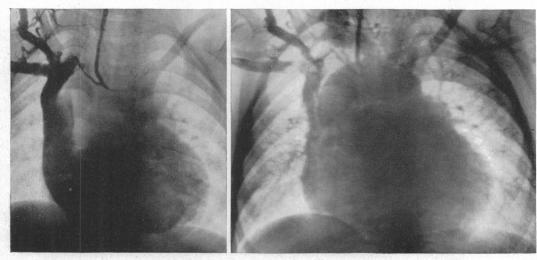

Cor biloculare.

Br Heart J. 1952 Jul;14(3):317-24. doi: 10.1136/hrt.14.3.317.